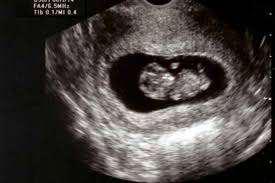

-Confirmar embarazo y edad gestacional -Localización del saco gestacional -Confirmar presencia de embrión o embriones y su vitalidad -PARTICULAR $35.000 -Valor preferencial FONASA: $30.000 **SUJETO A PROFESIONAL *Si tu atención es FONASA recuerda adjuntar tu certificado de afiliación al momento de reservar o llevarlo el día de tu atención